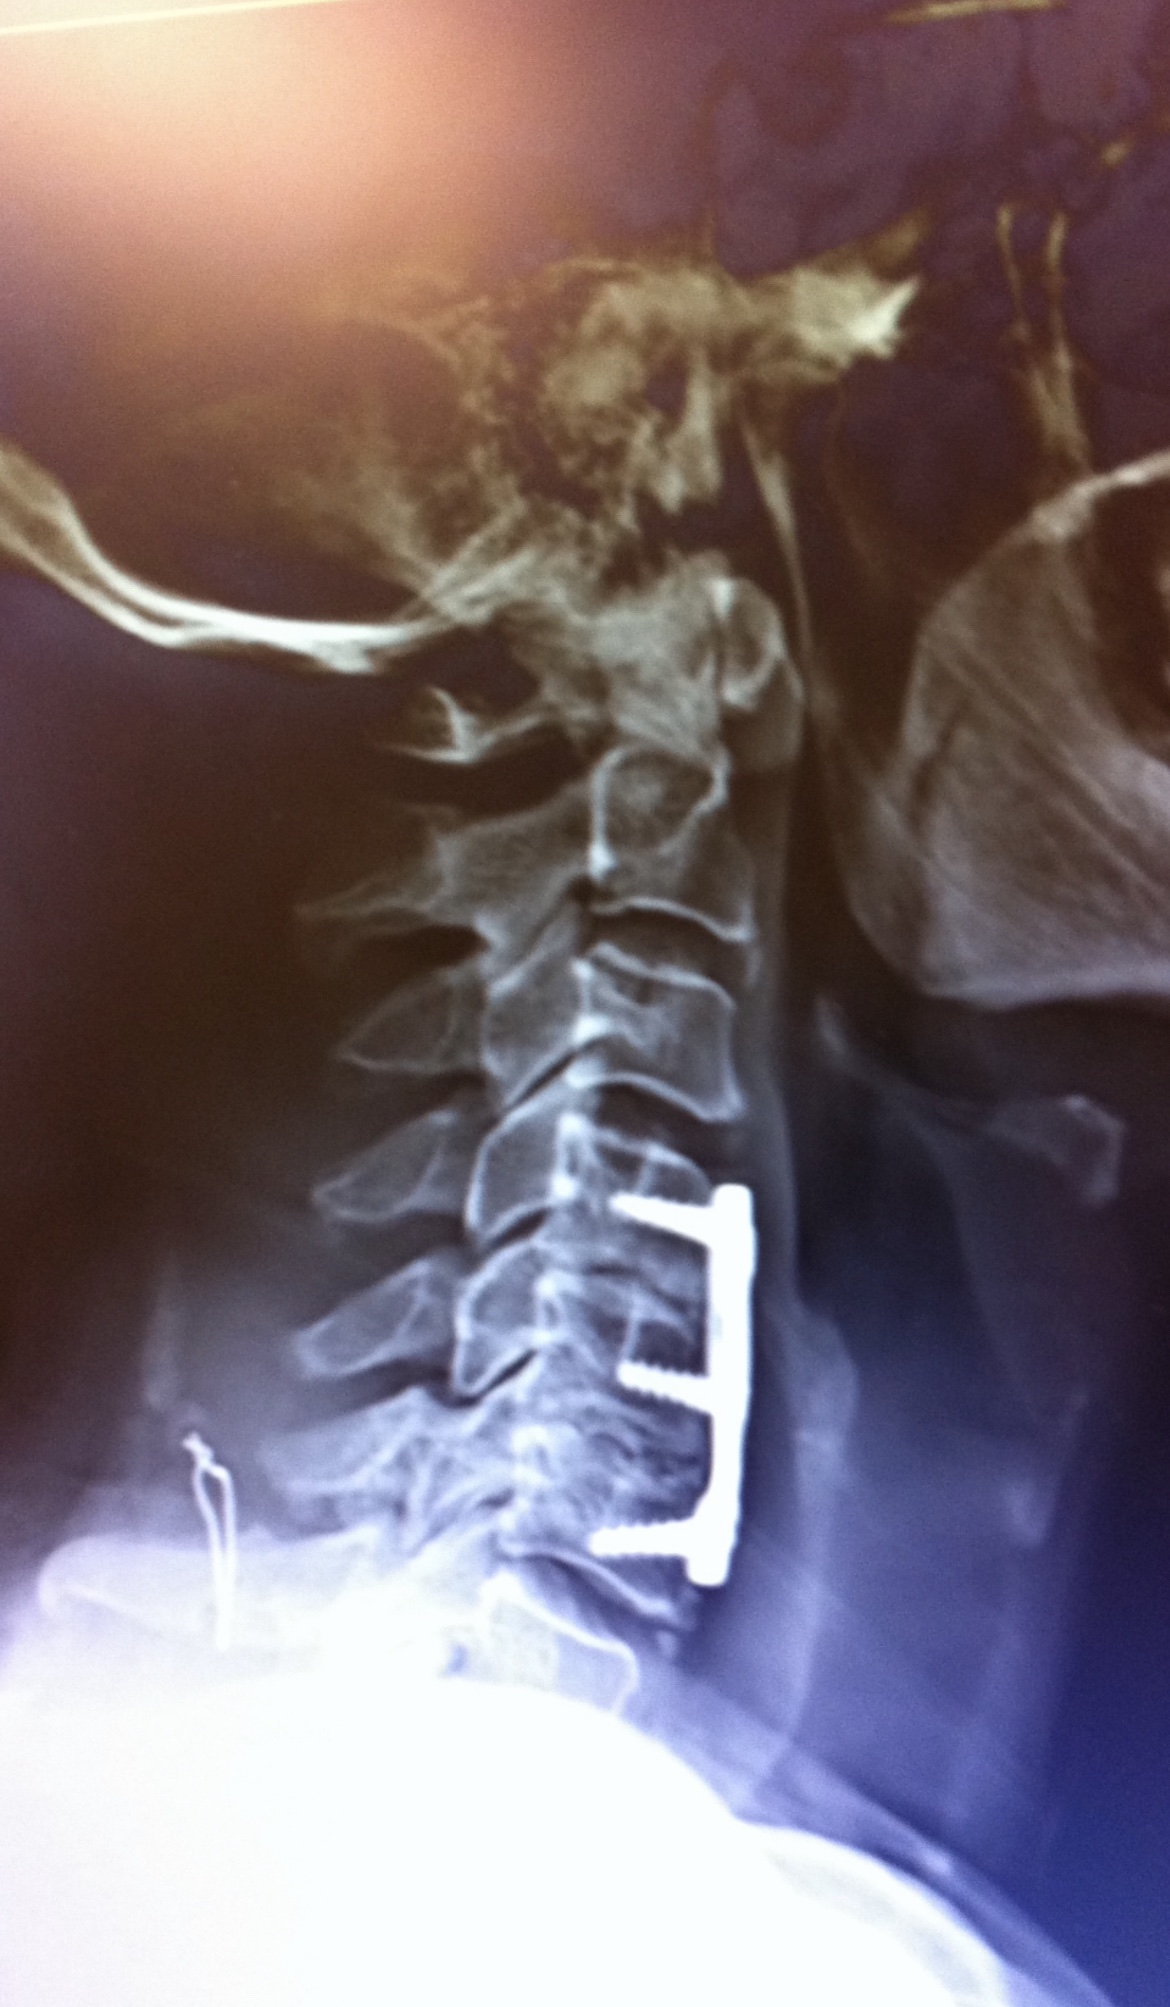

I took another photo, a side view, in which I could see the actual threads on the screws where they are tapped into the bone. I know this my seem a little gruesome to some of you, but Halloween is coming up and you see all kinds of skeleton pictures.

But what freaks me out about the side view photograph, it appears that the wire is hanging out in air, or in this case meaty flesh, because there is no bone showing up, nor is it attached to the metal pieces, as you can see in the photo below.

Like I said in the beginning I’m no doctor, but seriously this looks and feels like I got a piece of wire jabbing me in the neck. Isn’t that a piece of wire floating around with a sharp barb on the end? It sure feels like it.